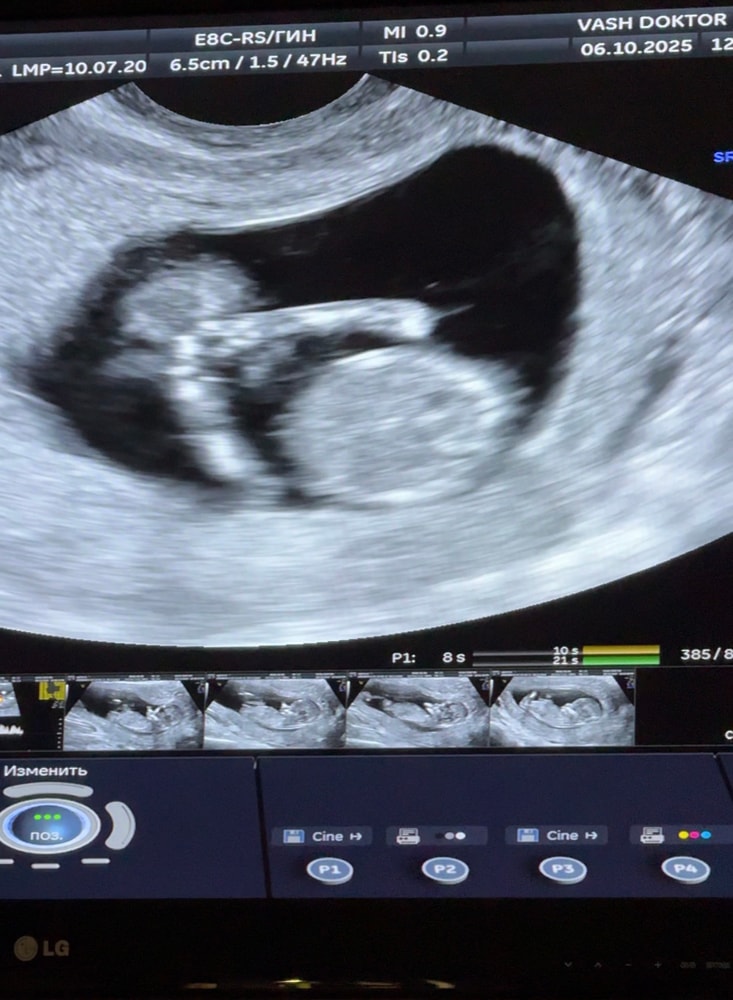

СкринингСегодня был 1й Скрининг - всё хорошо, мы здоровы по генетике)

Малыш догнал свой срок по М - 12+4 (была поздняя О, 5 дней опоздания)

КТР - 6,1 см

ТВП - 1,6

СБ - 165 уд/мин

Носовая кость есть, все пучком)

P.S. - в 12 часов дня человек спал😂 узист потыкала его датчиком в живот, он только сделал потягуси и дальше спать лег😂😂

на фото как раз закрылся ручками и дрых)